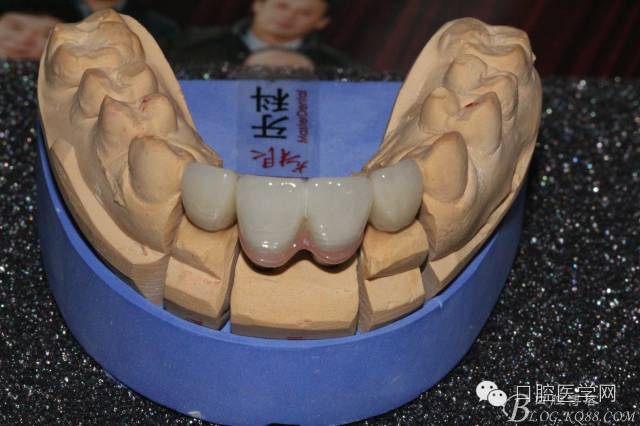

設計方案:11.21種植(選用登騰系統(tǒng),GBR植骨)12.22 RCT后樁冠修復,牙齦瓷修復。

因該患者笑線比較高,不微笑也露出牙齦,所以考慮到美觀,兩顆中切齒上方給做的牙齦瓷。